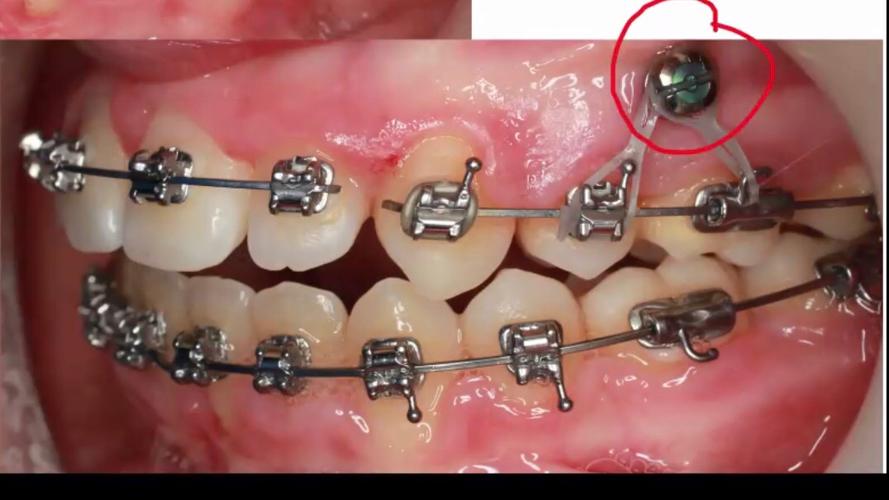

- 术区定位与标记:利用口内照片或CBCT影像,在患者口腔内标记植入点(通常位于牙根之间或附着龈充足的区域),确保植入位置避开牙根(至少1.5mm距离)、牙龈系带及骨性凹陷。

- 导向与植入:将支抗钉植入器尖端对准标记点,保持手机与牙面垂直(或根据骨面角度调整),低速(800-1200rpm)旋转植入,强调“手感反馈”——遇阻力时停止,避免强行穿透骨皮质,植入深度以钉头略低于牙槽骨平面为宜,便于后续正畸加力。

- 固定与检查:植入后用探针检查钉头稳定性,避免松动;若术中出血,可压迫止血或使用止血凝胶。

| 深度控制 | 钉头低于牙槽骨平面1-2mm,确保正畸加力时不压迫牙龈 | 过深可能导致植入困难,过浅易引发黏膜刺激 |

| 稳定性检查 | 植入后用镊子轻轻旋转钉头,确认无松动 | 若即刻松动,需调整位置或重新选择植入区 |